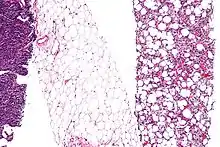

Dedifferentiation

Micrograph of a liposarcoma with some dedifferentiation, that is not identifiable as a liposarcoma, (left edge of image) and a differentiated component (with lipoblasts and increased vascularity (right of image)). Fully differentiated (morphologically benign) adipose tissue (center of the image) has few blood vessels. H&E stain.

Dedifferentiation, or integration, is a cellular process often seen in more basal life forms such as worms and amphibians in which a partially or terminally differentiated cell reverts to an earlier developmental stage, usually as part of a regenerative process.[14][15] Dedifferentiation also occurs in plants.[16] Cells in cell culture can lose properties they originally had, such as protein expression, or change shape. This process is also termed dedifferentiation.[17]